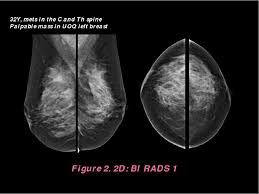

What Does Breast Cancer Look Like On A 3D Mammogram : Mammography 3d Mammography Tomosynthesis Densebreast Info Inc : Macrocalcifications, which look like small white dots on a mammogram.. To license this video for patient education or content marketing, visit: The doctor reading your mammogram will be looking for different types of breast changes, such as small white spots called calcifications, larger abnormal areas called masses, and other suspicious areas that could be signs of cancer. This overlapping tissue can cause the resulting image to look like cancer. Microcalcifications, which look like white specks on a mammogram. The tumor cells don't stay within the clear borders of the mass, but instead invade the nearby breast tissue.

Essentially, mammograms turn a 3d object into a 2d object. This is why you should always talk to your doctor if you notice an unexplained change in the size of a breast. What does the doctor look for on a mammogram? cancer.org. A screening mammogram is performed at regular intervals to check for breast cancer in women who have no signs or symptoms of the disease. Bright spots on a mammogram that look like potential tumors could turn out to be overlapping tissues or a blood vessel folding over on itself, friedewald said. To license this video for patient education or content marketing, visit: What does breast cancer look like? This overlapping tissue can cause the resulting image to look like cancer. Finding breast lumps and seeing change in the size and shape. Screening mammograms have been used since the 1980s. Digital breast tomosynthesis (tomo), also known as 3d mammography, is a revolutionary new screening and diagnostic breast imaging tool to improve the early detection of breast cancer. Ultrasound characterization of breast masses. indian journal of radiology and imaging. Calcifications are calcium deposits within the breast tissue and they look like small white spots.

More Breast Cancers Detected With 3d Mammography National Breast Cancer Foundation Nbcf Donate Online from 1o2l7w1aqqrk1f987e40vzis-wpengine.netdna-ssl.com This overlapping tissue can cause the resulting image to look like cancer. Several patterns of calcifications are seen with dcis, including: The look of breast cancer on a mammogram a tumor or lump will appear as a focused white area on the mammogram. Most screening mammograms include two views of each breast taken from different angles. Specialist doctors (radiologists) trained to interpret mammograms can identify any abnormal areas, masses or calcium. What does breast cancer look like on a mammogram? A tumor that is benign, it is not a health problem and it may not grow or change shape. Ultrasound characterization of breast masses. indian journal of radiology and imaging.

Breast cancer and some noncancerous (benign) breast conditions can appear white on a mammogram. This overlapping tissue can cause the resulting image to look like cancer. Diagnostic mammograms involve taking more views than screening mammograms. It's so important to listen to the messages our bodies are telling. A number of studies have found that 3d mammograms find more cancers than traditional 2d mammograms and also reduce the number of false positives. Ultrasound characterization of breast masses. indian journal of radiology and imaging. Even if you have a lump in only one breast, pictures will be taken of both breasts. Finding breast lumps and seeing change in the size and shape. 1 the gray areas correspond to normal fatty tissue, while the white areas are normal breast tissue with ducts and lobes. A false positive is when a mammogram shows an abnormal area that looks like a cancer but turns out to be normal. Breast cancer can appear as a spiculated mass, cluster of tiny calcifications, smoothly marginated mass, area of subtle distortion or be invisible on. Macrocalcifications, which look like small white dots on a mammogram. One advantage of ultrasound technology is that it allows substantial freedom in obtaining breast images from any orientation.